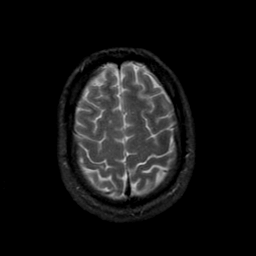

MR Study #23, January 26, 1992 -- Slice #41